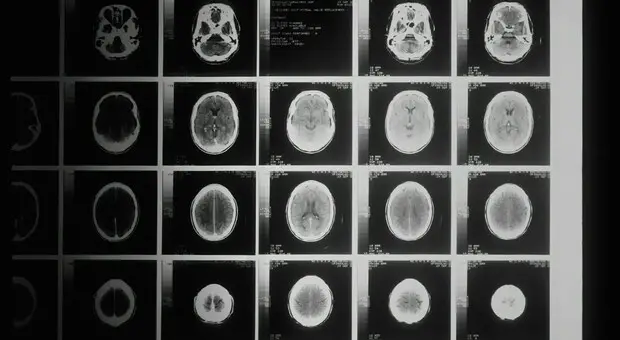

Tumore al cervello, una nuova terapia 'personalizzata' contro il glioblastoma: rallenta nel 70% dei casi

Il glioblastoma è una delle forme di tumore cerebrale più aggressiva ed è molto difficile da trattare, soprattutto perchè non risponde ai trattamenti con strategia...